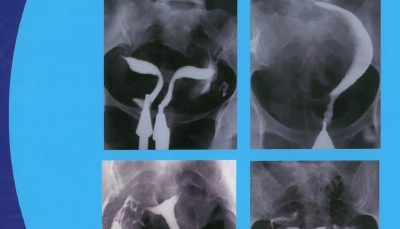

A Textbook and Atlas of Hysterosalpingography Second Edition (هیستروسالپنگوگرافی)

تالیف:

َAhmad Vosough, Gholam Shahrzad, Firoozeh Ahmadi, Fatemeh Zafarani, Fatemeh Pahlavan, Fereshteh Hosseini

نویسنده

700,000 تومان